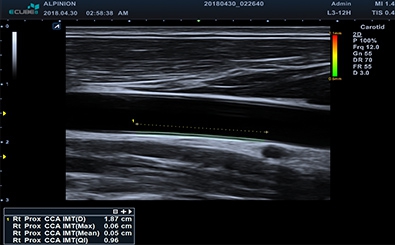

Auto IMT